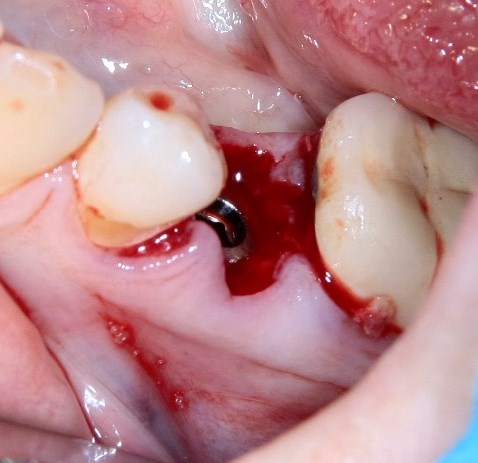

Немедленная имплантация — оптимальное решение в любой клинической ситуации